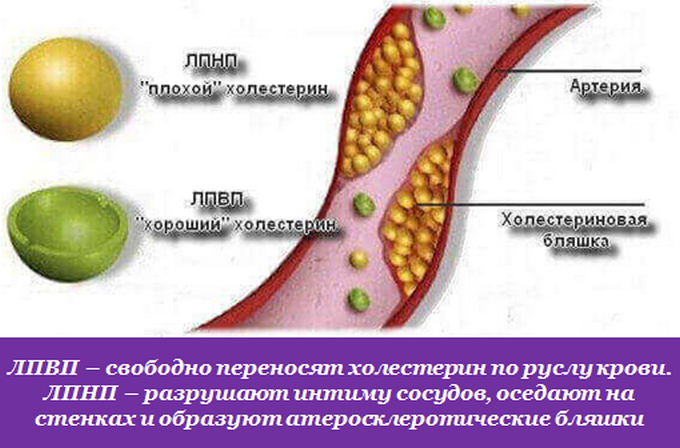

Холестерин в организме: влияние и функции (схемы и диаграммы)